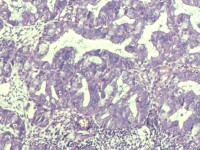

性别

女

年龄

55岁

临床诊断

异常子宫出血

一般病史

阴道不规则出血1月

标本名称

子宫内膜

大体所见

灰白色组织1堆、4*3.4*2.2CM大。

能诊断癌吗

子宫内膜样腺癌